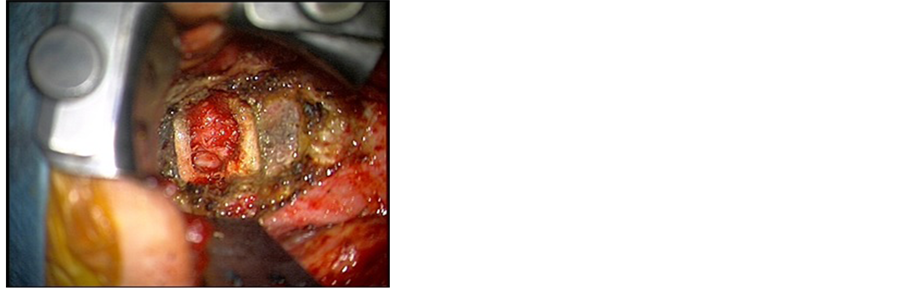

Post-operatively the patient was kept intubated for five days after which a successful extubation was performed. The NG tube was kept in place for six weeks. A transitory proximal lower extremities weakness was noticed when ambulating the patient but eventually recovered three weeks later with the help of physiotherapy and aggressive rehabilitation (Figure 8(a), Figure 8(b)). Intra-operative cultures revealed heavy growth of Candida albicans for which fluconazole (400 mg per day for six weeks) was added to the treatment. Six months later patient presented to clinic for follow-up had significant improvement in her muscle tone. Barium swallow

Figure 8. (a) Post operation T2 WI MRI; (b) Post operation T1 WI MRI.